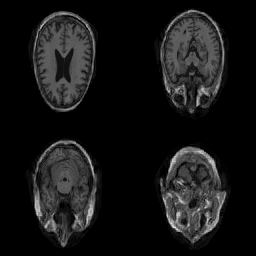

| Original | Renderings after de-identification | Original | MRI slices after de-identification | ||||||

| CP-GAN | FACE MASK | DEFACE | QUICKSHEAR | CP-GAN | FACE MASK | DEFACE | QUICKSHEAR | ||

Benchmark De-Identification Methods. We compare our result with three publicly available and widely-established methods for de-identification of MRI head scans, depicted in Figure 3. All methods have in common that they (1) are not deep-learning-driven, (2) require no additional training and (3), are used on a day-to-day basis in neuroscience and clinical research. All procedures were applied with default settings on images of resolution . The methods include QUICKSHEAR [Schimke et al.(2011)Schimke, Kuehler, and Hale], FACE MASK [Milchenko and Marcus(2013)], and DEFACE [Bischoff-Grethe et al.(2007)Bischoff-Grethe, Ozyurt, Busa, Quinn, Fennema-Notestine, Clark, Morris, Bondi, Jernigan, Dale, Brown, and Fischl]. Descriptions of the methods are provided in the Appendix. We also include MRI WATERSHED [Ségonne et al.(2004)Ségonne, Dale, Busa, Glessner, Salat, Hahn, and Fischl], a skull-stripping method that removes everything except the brain.